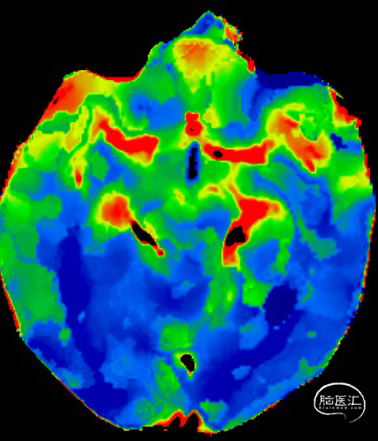

术前CTP提示后循环缺血,Tmax、MTT延长,CBF、CBV未见明显改变。